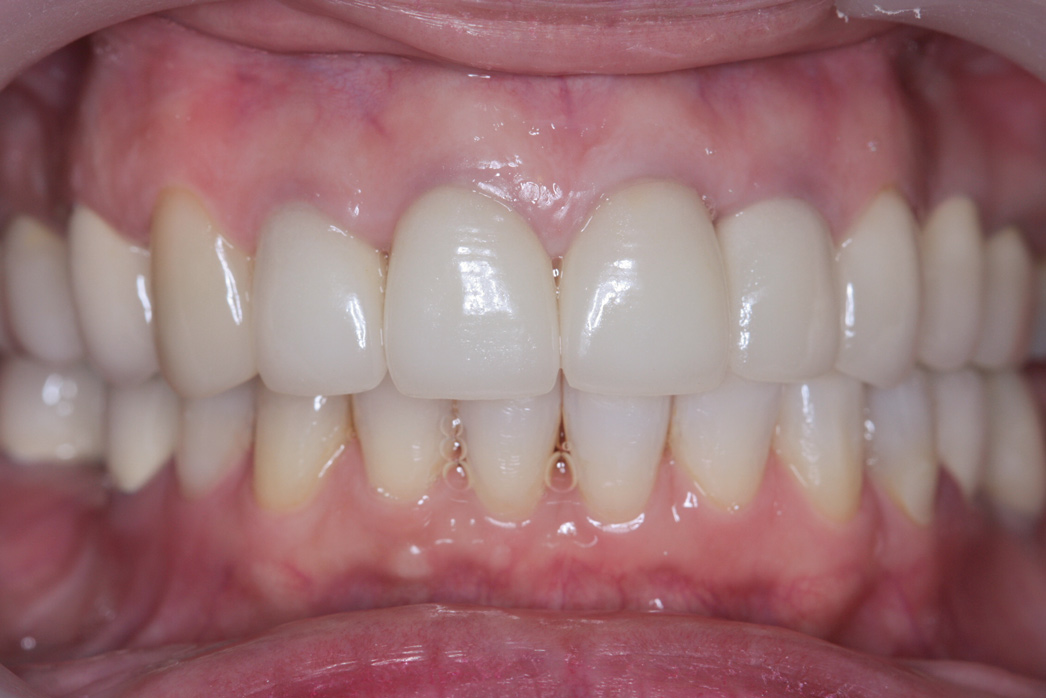

Post-treatment records showed a dramatic improvement in the patient's profile, smile, and dental esthetics and occlusion. The modified VDO had significantly increased the LAFH to achieve better facial proportion (UAFH/LAFH ratio of 50%/50%) and caused the depression of her chin to become shallower (Figure 9 and Figure 10). Intraorally, class I occlusion with well-aligned arch form and ideal overjet and overbite, esthetic upper anterior teeth size and proportion, good gingival margins, and proper prosthetic restorations were all achieved (Figure 11 and Figure 12).

Fig 11. Intraoral frontal view after treatment.

Figure 11